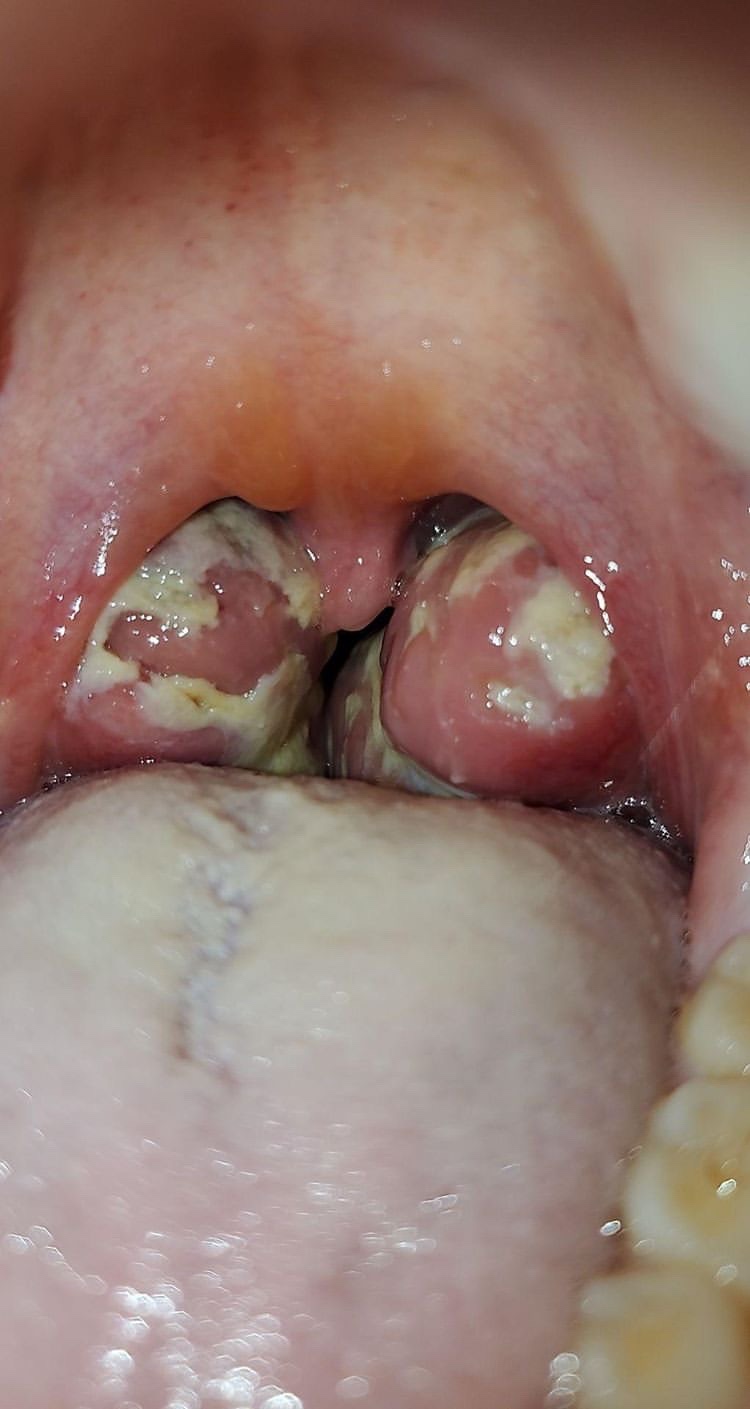

Nasty Throat Gallery Nasty Throat By Nicole Angemi|2026-01-07T09:01:04-05:00September 19th, 2020|The Gross Room, MEDICAL, Chronic Medical Conditions| Read More 29